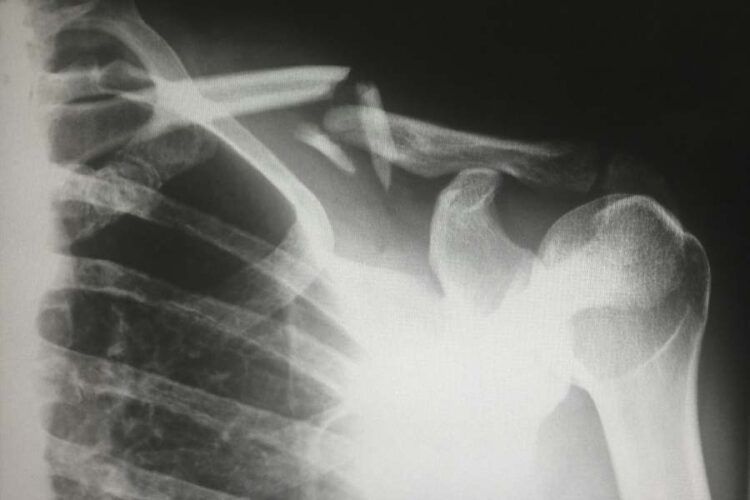

Neck and spinal cord injuries

The agony and nerve damage from the spinal cord and cervical injuries can significantly impair a person’s range of motion, if not paralyze them. These injuries are also very serious and permanent in most cases.

Vehicle accidents are among the most common causes of catastrophic injuries. They can lead to traumatic brain injuries, spinal cord injuries, and many fractures, especially when driving at high speeds. When speaking about car accidents, those involving head-on collisions, T-bones, and rollovers are the greatest threats. People can suffer from brain damage, spinal cord injuries, internal bleeding, and other traumas in such cases. Motorcyclists are also in great danger, especially if they don’t wear protective equipment. Then, the sheer size and weight of a big truck make these vehicles very dangerous, and people in smaller cars are in life danger if they get into an accident with these big boys.

Falls are among the leading causes of catastrophic injuries and can happen to any one of us and almost everywhere. For example, wet floors, uneven surfaces, or dim lighting can all cause slip-and-fall accidents that lead to hip fractures, spinal cord injuries, and traumatic brain injuries. Also, falls from heights can even be fatal, and workers who clean windows and work on construction sites are especially vulnerable.